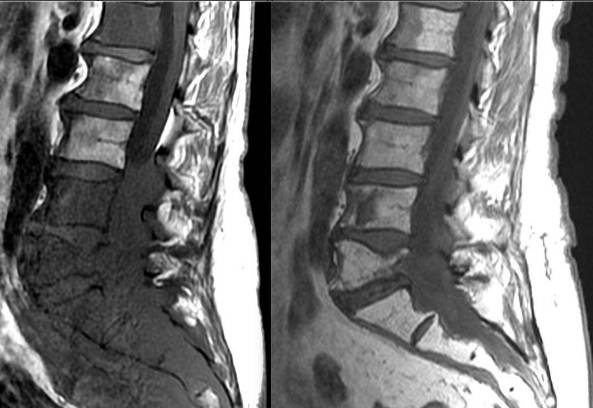

Злокачественные новообразования

Саркома Юинга чаще всего поражает детей и подростков.

Шишки на спине могут возникать из-за раковых опухолей. Они бывают первичными, возникающими из патологий позвоночника, и вторичными, связанными с метастазами. Хотя рак позвоночника встречается редко, его нельзя исключать. Поэтому при любых подозрениях на патологию следует обращаться к специалисту.

К наиболее распространенным злокачественным опухолям в области спины относятся:

- саркома Юинга – возникает в детском возрасте и поражает спинной мозг;

- хондросаркома – затрагивает хрящевые ткани;

- хондрома – развивается в хорде и чаще встречается у людей среднего и пожилого возраста;

- остеосаркома – возникает в позвонках;

- миелома – приводит к разрушению нервных клеток и тканей позвоночника.

Метастазы в костных тканях могут развиваться при злокачественных новообразованиях молочных желез, почек, простаты и щитовидной железы. Уплотнение на позвоночном столбе чаще всего можно нащупать, если оно развивается в переднем направлении. В других случаях его обнаруживают во время диагностики или на поздних стадиях.